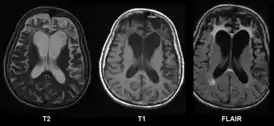

![]() МРТ при болезни Пика | |

При гистологическом исследовании ткани головного мозга в нейронах обнаруживаются необычные включения. Пирамидные нейроны набухшие, содержат цитоплазматические тельца Пика. Толщина серого вещества снижена, граница между серым и белым веществом размыта. Отмечается расширение желудочков (преимущественно передних рогов боковых желудочков) и субарахноидального пространства, углубление борозд полушарий.